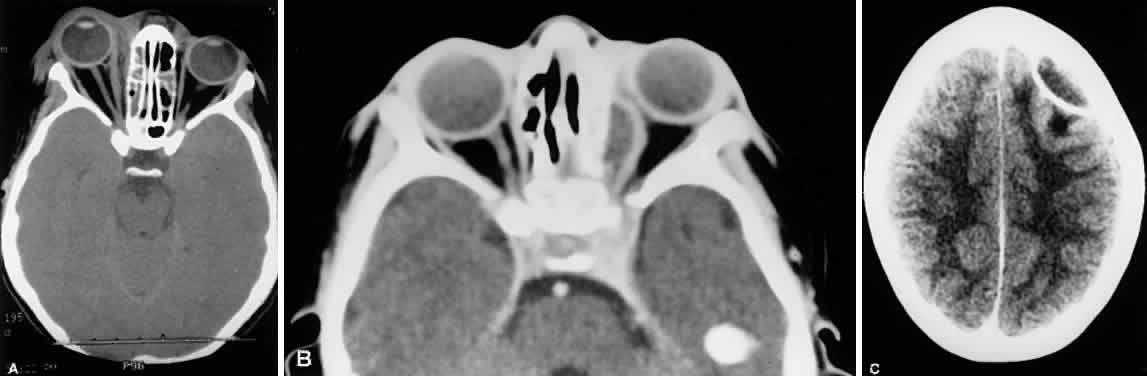

The cardinal signs and symptoms of orbital cellulitis are proptosis and ophthalmoplegia. Pain on eye movement, decreased vision, conjunctival chemosis, and elevated intraocular pressure are common but variable accompanying signs (Fig. 21). The first ocular sign of sinusitis may be preseptal inflammation only; this can then quickly progress to the classic clinical picture of orbital cellulitis. Ethmoid sinusitis is by far the most common cause of orbital cellulitis.45–48

Fig. 21. Fourteen-year-old boy with right orbital cellulitis secondary to ethmoid sinusitis. There is tense swelling of the upper lid, proptosis, chemosis (A), limited adduction (B), and limited abduction (C).